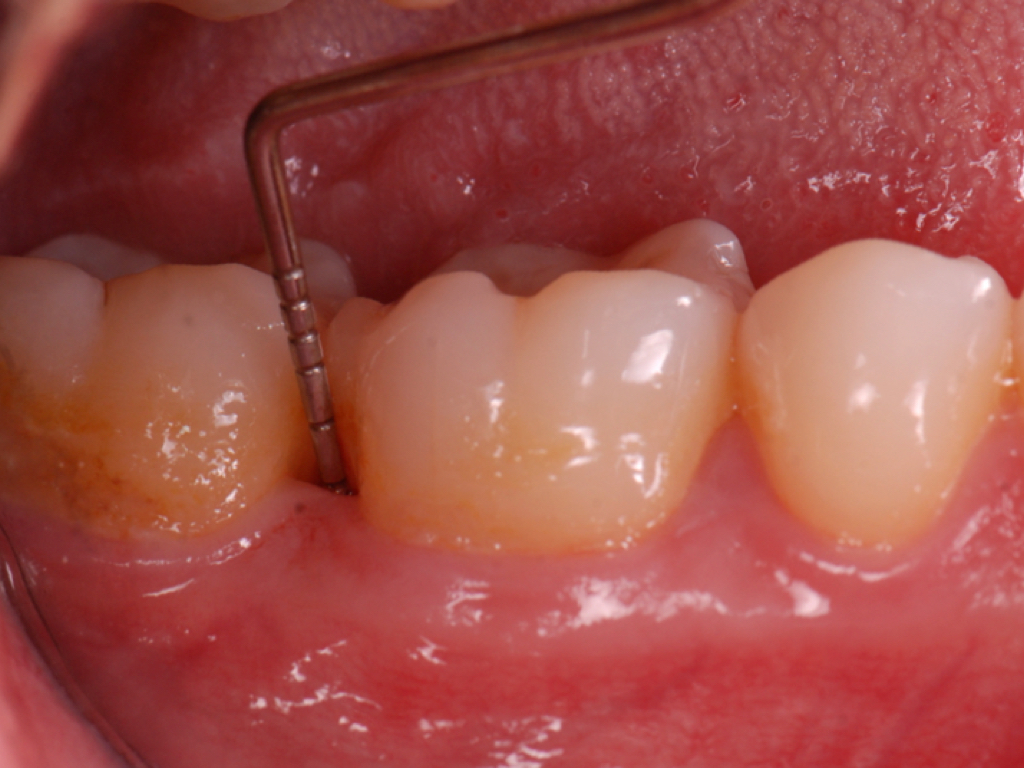

Clinical PPD is measured to the nearest millimeter by means of a graduated periodontal probe with a standardized tip diameter of approximately 0.4 mm to 0.5 mm. Several factors can influence the measurements made with periodontal probes, including: the thickness of the probe used5; the angulation and positioning of the probe depending on anatomic features, such as the contour of the tooth surface (Figure 1 through Figure 3)6; the graduation scale of the probe5; the pressure applied on the instrument during probing6; and the degree of inflammatory cell infiltration in the soft tissue and accompanying loss of collagen.7

Fig 1. Inaccurate probing angle wrongly indicates probing depth at 3 mm, which does not correspond to the radiographic finding shown in Fig 2.

Figure 1

Fig 3. Correct angulation of the probe demonstrates 6-mm probing depth.

Figure 3